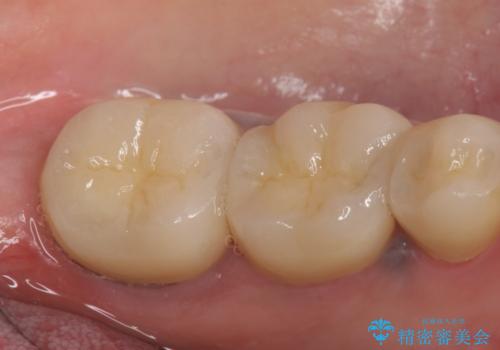

症状の消失を確認後、オールセラミッククラウンによる補綴を行いました。

今回用いたオールセラミッククラウンは、ジルコニアフレームという白い素材の上にセラミックを盛っているため審美性が非常に高いのが特徴です。

またジルコニアは人工ダイヤモンドの材料にも使われているほど高い強度を持っており、そのためオールセラミッククラウンは審美性だけでなく、奥歯やブリッジの補綴も可能とするクラウンです。